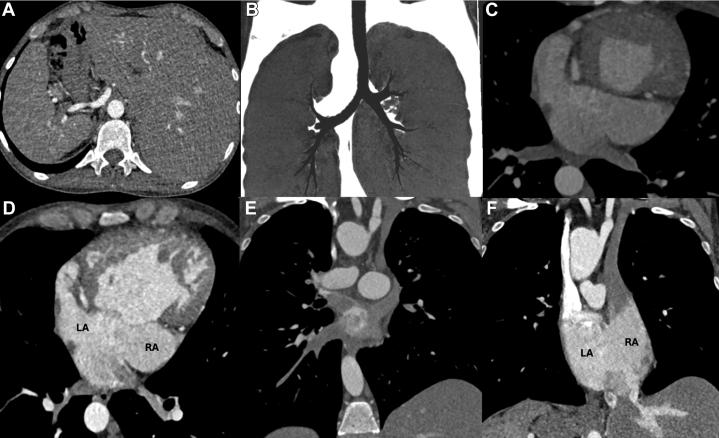

Double-Outlet Right Ventricle in an Adult With a Univentricular Heart and Total Situs Inversus.

Double-outlet right ventricle is a complex conotruncal anomaly in which both great arteries arise predominantly from the right ventricle. The coexistence of total situs inversus and univentricular physiology is exceedingly rare.

CASE SUMMARY

A 38-year-old man presented with severe chronic cyanosis (baseline oxygen saturation 65%), NYHA functional class III dyspnea, and right-sided heart failure. Multimodal imaging (echocardiography, CT, and cardiac magnetic resonance) confirmed total situs inversus, a markedly hypoplastic left ventricle anatomically isolated by a muscular ridge, and double-outlet right ventricle with moderate subpulmonary stenosis. His condition was stabilized medically, but surgical risk was deemed prohibitive owing to his univentricular physiology.

DISCUSSION

This case underscores the critical importance of comprehensive imaging for delineating complex intracardiac anatomy and illustrates how moderate subpulmonary stenosis can temper pulmonary overcirculation, thereby prolonging survival.

TAKE-HOME MESSAGE: Meticulous anatomical definition is essential for managing rare adult congenital heart disease.